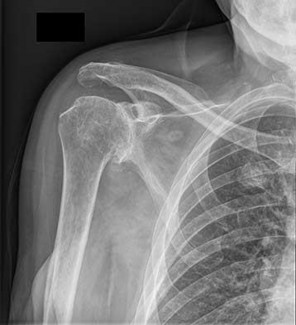

Question 10:

According to recent quantitative anatomical studies utilizing MRI and gadolinium, which of the following vessels provides the principal intraosseous blood supply to the humeral head, challenging historical teachings regarding proximal humerus vascularity?

Options:

- Anterior humeral circumflex artery

- Posterior humeral circumflex artery

- Suprascapular artery

- Thoracoacromial artery

- Circumflex scapular artery

Correct Answer: Posterior humeral circumflex artery

Explanation:

Historically, the anterior humeral circumflex artery (via its arcuate branch) was thought to be the primary blood supply to the humeral head. However, modern quantitative studies (e.g., Hettrich et al.) have demonstrated that the posterior humeral circumflex artery provides the vast majority (approximately 64%) of the intraosseous blood supply to the humeral head.

Question 32:

A 28-year-old male presents after an unprovoked seizure. He complains of right shoulder pain and is unable to externally rotate his arm. Imaging confirms a posterior shoulder dislocation. Further evaluation reveals an impaction fracture of the humeral head known as a reverse Hill-Sachs lesion. Where is this articular defect classically located?

- Posterolateral aspect of the humeral head

- Anteromedial aspect of the humeral head

- Posteromedial aspect of the humeral head

- Anterolateral aspect of the humeral head

- Central articular surface of the humeral head

Correct Answer: Anteromedial aspect of the humeral head

A posterior shoulder dislocation commonly results in an impaction fracture of the humeral head as it is driven against the posterior glenoid rim. This defect is known as a reverse Hill-Sachs lesion and is classically located on the anteromedial aspect of the humeral head. In contrast, an anterior dislocation produces a standard Hill-Sachs lesion, which is located on the posterolateral aspect of the humeral head.